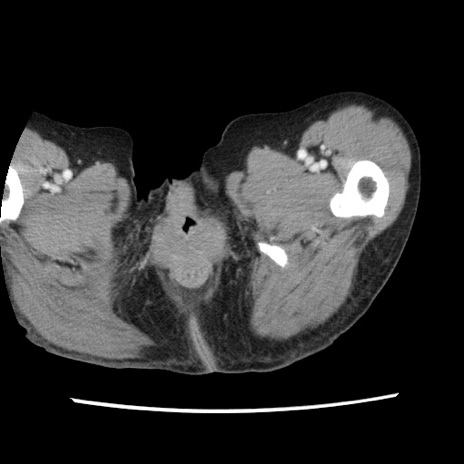

【症例】80歳代女性

【主訴】腹痛

【現病歴】8時間前から腹痛あり来院。

【既往歴】糖尿病、脂質異常症、子宮体癌にて子宮全摘術

【身体所見】意識清明・会話良好だが腹痛で苦悶様、全腹部にわたって反跳痛と圧痛あり

【データ】WBC 13600、CRP 0.14、LDH 224、CK 90